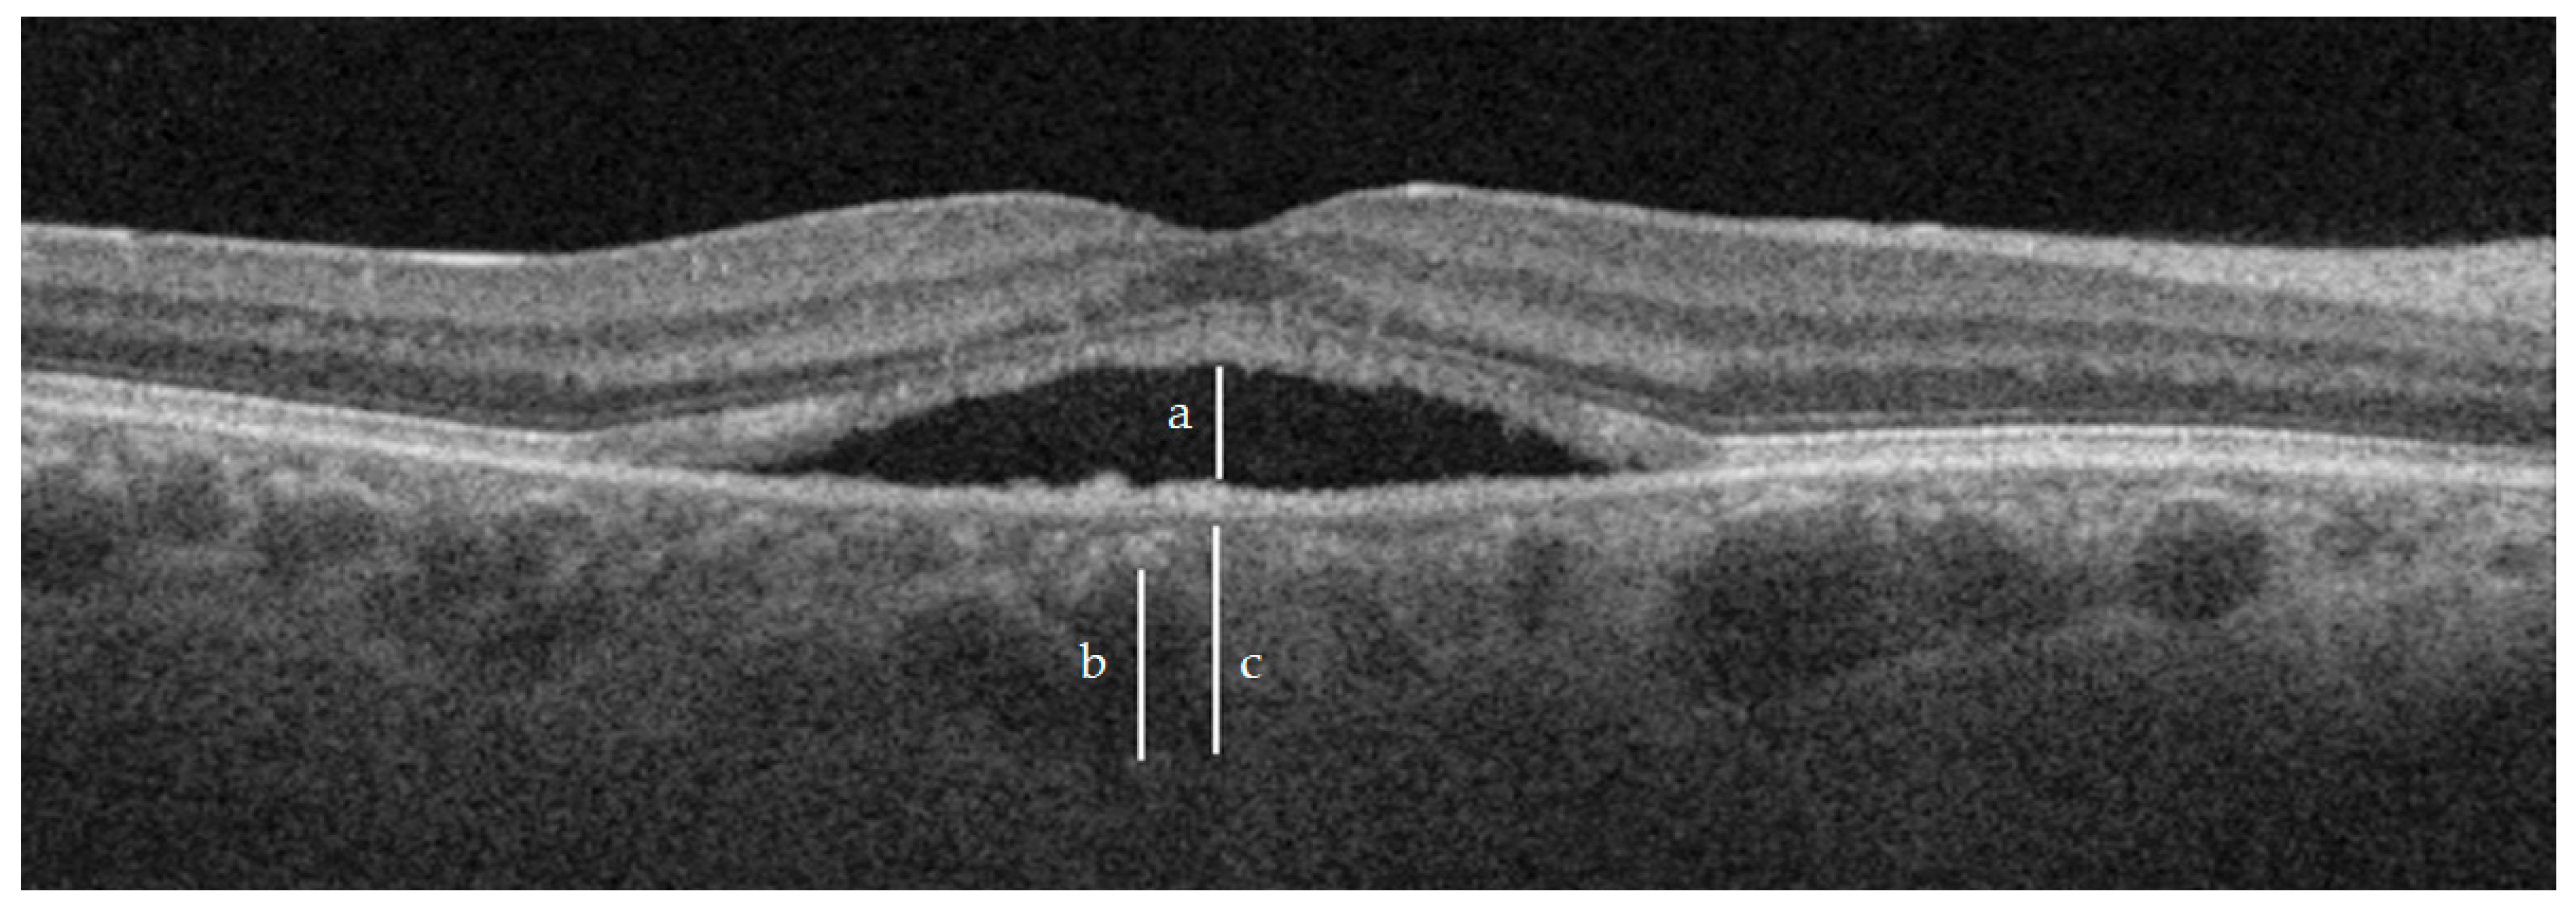

3.1. Subretinal Fluid (SRF)

3.3. Choroidal Thickness (CT)